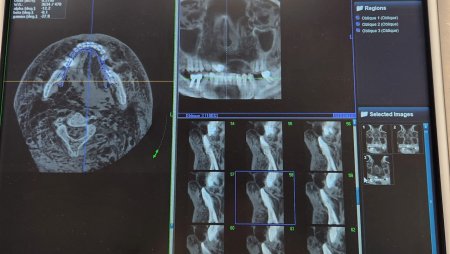

Мы делаем снимки, зовем команду. И они увозят одно и завозят следующее тело.

Те, кого мы отсканировали, перекладывают в деревянный ящик и увозят. И так без остановки. Опознание идет, как я уже писала, круглосуточно, но медленно.

Идентификация останкоыв погибших. Фото: Инна Рысина

Автор: Инна Рысина. Рентгенолог